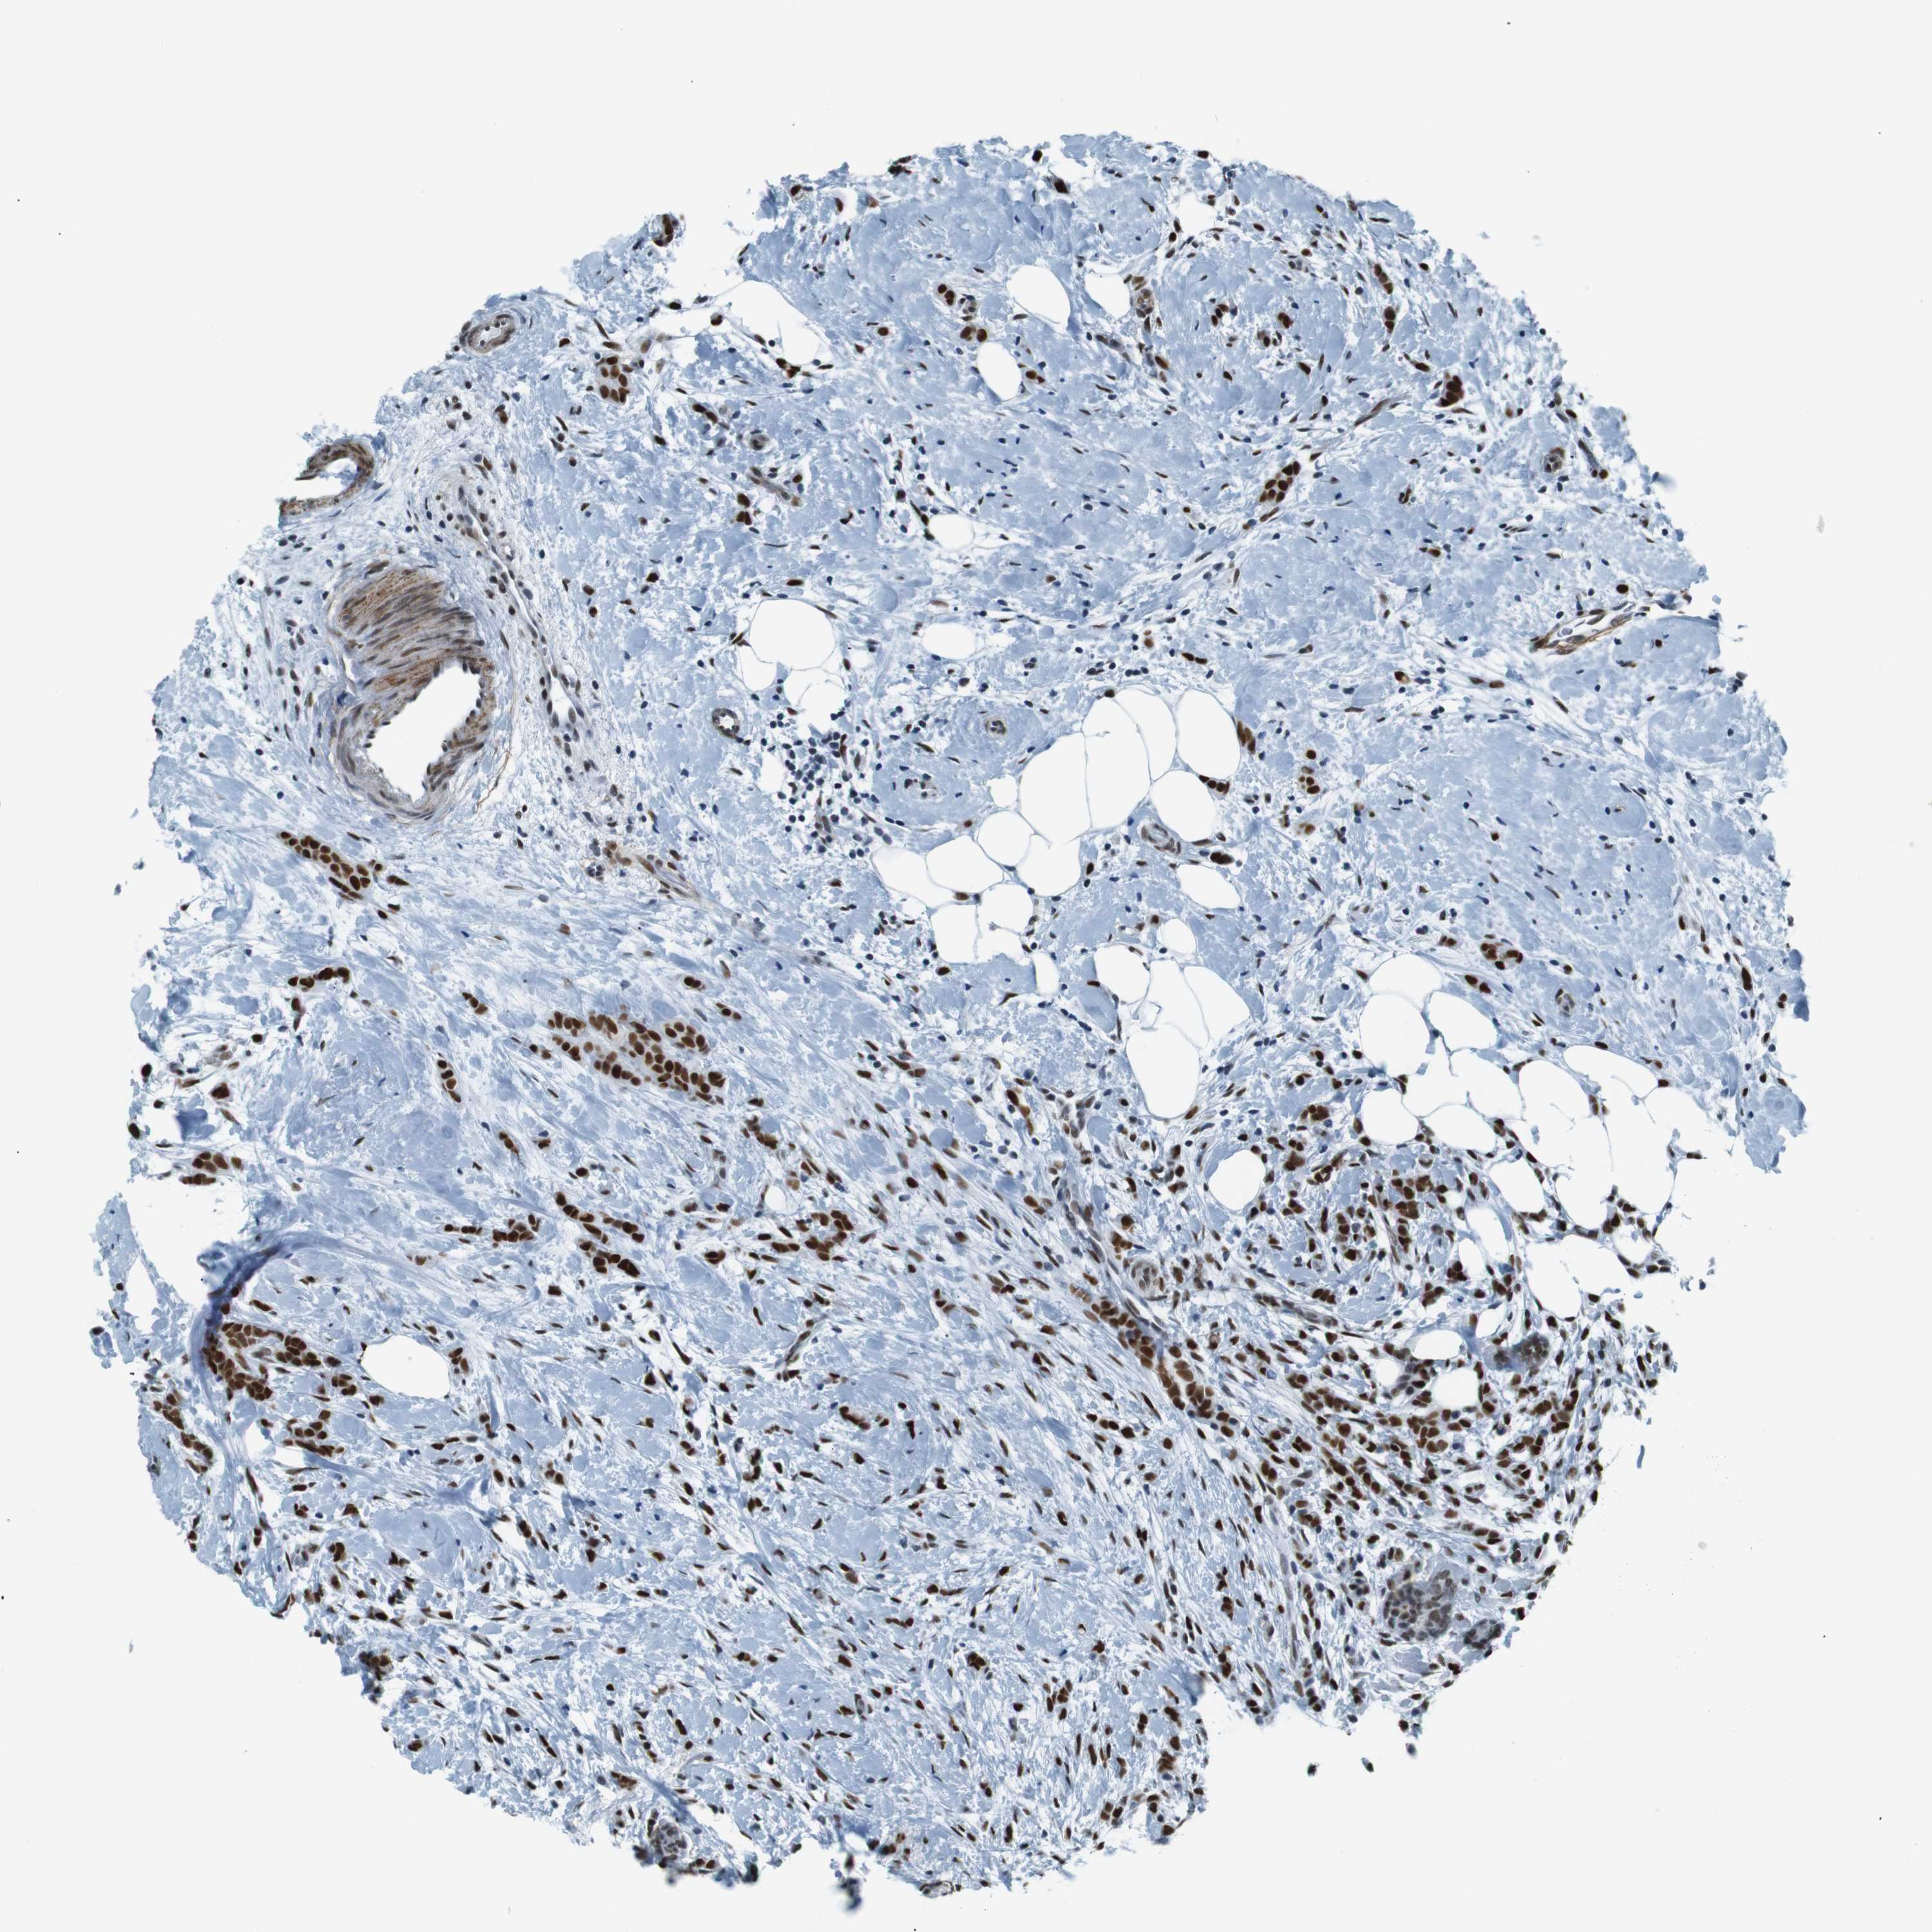

CANCER BREAST CANCER Show tissue menu

BRCA TCGA BRCA VALIDATION PROTEIN EXPRESSION